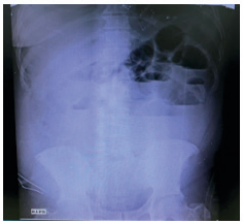

Del centro remisor trae el reporte de hemograma extrainstitucional con evidencia de leve leucocitosis con neutrofilia y parcial de orina no patológico. Ecografía de abdomen total que documenta asas colónicas de paredes engrosadas con discreto edema interesa compatible con colitis. Se realiza una radiografía de abdomen en bipedestación (figura 2), que evidencia la dilatación de asas intestinales delgadas, engrosamiento de pared con presencia de múltiples niveles hidroaéreos y asa centinela en hipocondrio izquierdo.

Radiografía de abdomen en bipedestación